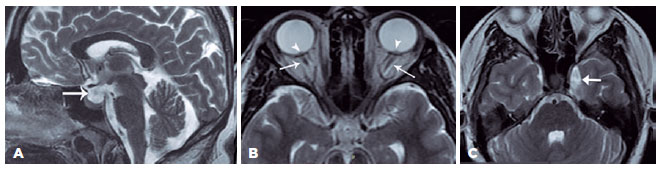

A neurological examination revealed no pathological findings. Cranial magnetic resonance (MR) imaging demonstrated partially empty sella, asymmetric dilatation of the left cavernous sinus, prominent subarachnoid space, and optic disc bulging, suggesting papilledema (Figure 4). MR venography was normal. These imaging results suggest idiopathic elevated ICP in the proper clinical settings. The cerebrospinal fluid (CSF) opening pressure was 310 mmH2O. The patient was diagnosed with PTCS and oral acetazolamide 1 g/day was administered. Visual obscurations, diplopia, and headache improved in two weeks, and tinnitus disappeared completely at six months. Blindspot enlargement on VFE and bilateral papilledema resolved after 2.5 months of treatment (Figure 3).

In our present case, PTCS was diagnosed based on signs and symptoms of increased ICP, papilledema on fundoscopy and OCT examinations, and normal findings on cranial neuroimaging and high CSF opening pressure(1). The key diagnostic MR imaging features of the idiopathic intracranial hypertension included normal or decreased size of the ventricular system, partially empty sella, flattening/indentation of the posterior sclera, prominent optic nerve sheaths, and optic nerve tortuosity. Bilateral transverse sinus stenosis is associated with 90% of cases. The differential diagnosis of the disease may include mild cerebral edema, empty sella syndrome, and hypoplastic dural venous sinuses(10).